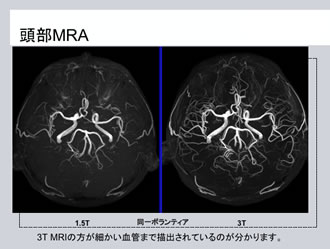

専用 脳MRI 3 高性能MRI(1.5テスラ)|施設・設備|おおたけ脳神経・漢方内科の詳細情報

高性能MRI(1.5テスラ)|施設・設備|おおたけ脳神経・漢方内科。今回導入された3T-MRIについて|名古屋セントラル病院。1.5T MAGNETOM ESSENZA 頭頸部領域における質の高い診断と検査。